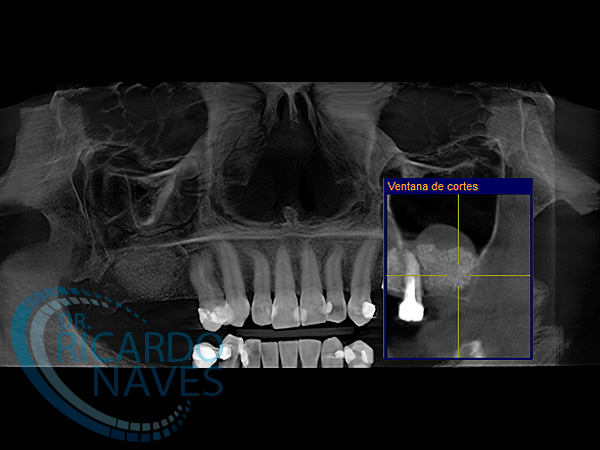

Elevación de seno maxilar técnica de ventana lateral.

Antes y después de elevación de seno bilateral. 5 meses de evolución. Obsérvese la cantidad de hueso que podemos ganar  en estas verdaderas cajas biológicas.